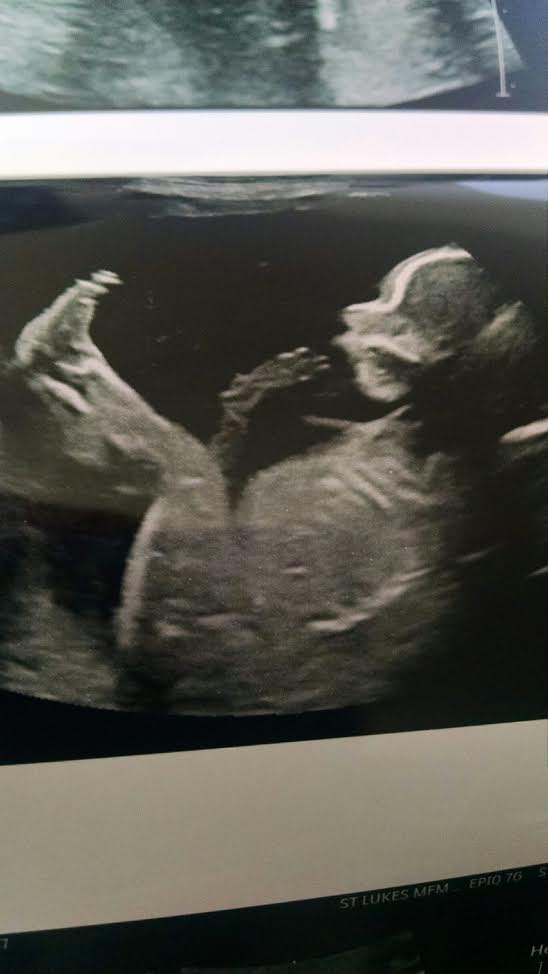

Maybe girl?

The skull looks girly to me as well (and I thought this before I read Claire's post) - I hope I am right.